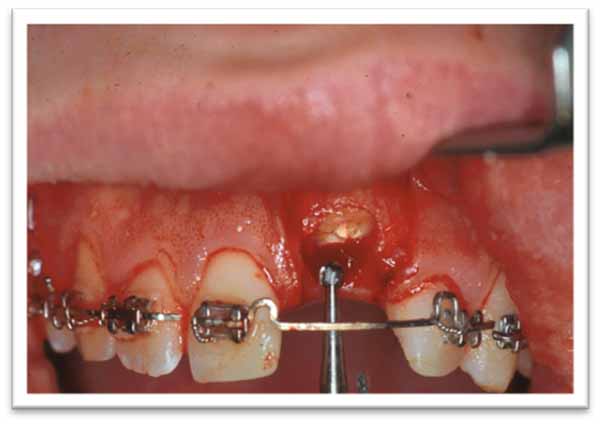

- 治療中は、エナメル質をすべて除去することが重要です。また、残存する根管充填材も除去し、根管を血液で満たす必要があります。(画像2および3は、2人の患者における外科的処置の原則を示しています。)

画像2.患者2:21 番の歯のクラウンの準備。頬側の粘膜骨膜フラップが反り返っています。クラウンがちょうど除去されたところです。その後、根管充填材が除去され、根管は血液で満たされ、歯茎は縫合されます。

画像3. 患者3:骨性癒着11番の修復。頬側の粘膜骨膜フラップが反転されています。治療中に歯冠が除去されるため、エナメル質が残っていないことを確認することが重要です。薄い象牙質層は残しておくことが有益です。修復が完了したら、フラップを縫合します。